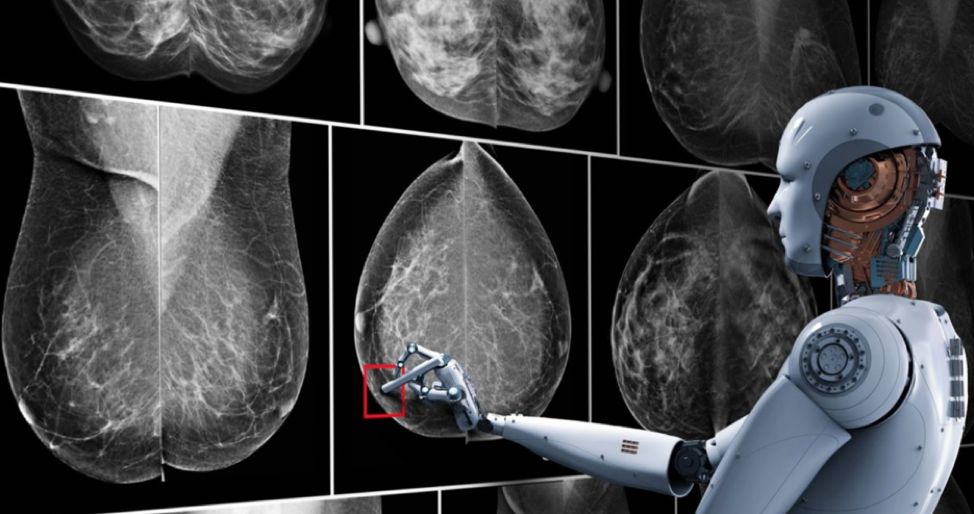

让一个机器人透视你的身体,洞察你体内的蛛丝马迹,比经验丰富的老教授更快更准地找出你的沉疴暗疾,你是会觉得惊悚还是幸运?

(AI医疗影像诊断,图片来自Nvidia)